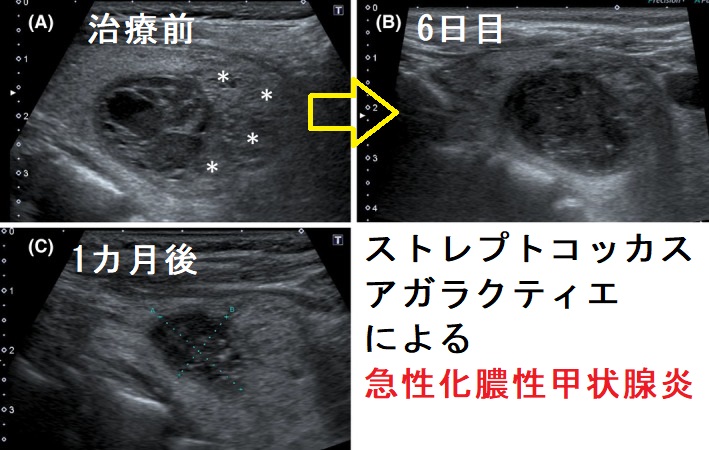

ストレプトコッカス・アガラクチア(ストレプトコッカスアガラクティエ、Streptococcus agalactiae)はGBS【B群溶血性連鎖球菌】の一種です。

糖尿病患者では膿瘍、蜂窩織炎、糖尿病壊疽の原因になります。

産道感染による新生児髄膜炎が有名です。糖尿病妊婦では子宮内への上行性感染で早産・早期破水・絨毛羊膜炎(38度以上の発熱、早産の原因)・産褥期敗血症を、糖尿病男性では前立腺炎があります。

妊娠末期(35~37週)の腟分泌物細菌培養検査でB 群連鎖球菌(GBS)が陽性となった妊婦には、母子感染予防対策として、陣痛開始時(分娩の4時間以上前)にペニシリン系抗菌薬投与を開始。

糖尿病の免疫不全では敗血症/内因性眼内炎による失明、感染性心内膜炎が報告されます。糖尿病性感染性心内膜炎はストレプトコッカス・アガラクチアがもっとも多いとの報告があります。

ストレプトコッカスアガラクティエによる急性化膿性甲状腺炎の報告があります[Clin Case Rep. 2017 Jun 19;5(8):1238-1242.]